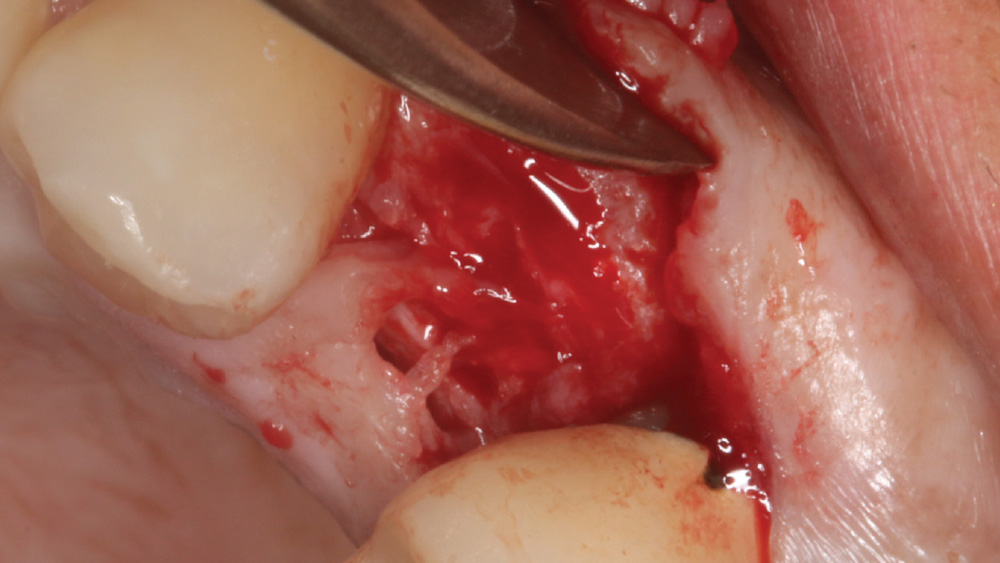

When the attached tissue is minimal, a flap procedure allows the surgeon to reposition the flap to create more attached gingiva and improve the interdental papillae at the implant site. Reflecting a gingival flap also enables the practitioner to more clearly see the final position of the implant at the crest of the bone. If it’s necessary to visualize the bone during the surgical procedure due to uncertain ridge width or height, flap reflection is the safest, most predictable approach.

CASE REPORT

The following case, which I performed alongside Dr. Stephanie Tilley of Pensacola, Florida, illustrates the use of both surgical techniques for the same patient, who presented with edentulous spaces in the areas of both right and left maxillary first bicuspids. Due to varying soft-tissue volume on each side of the arch, implant surgery was performed using a flapless procedure for one site, while the attached gingiva was reflected to expose the available hard tissue for the other. As a result of proper site evaluation, treatment planning and restorative-driven implant placement, both surgical techniques led to successful outcomes for the patient.